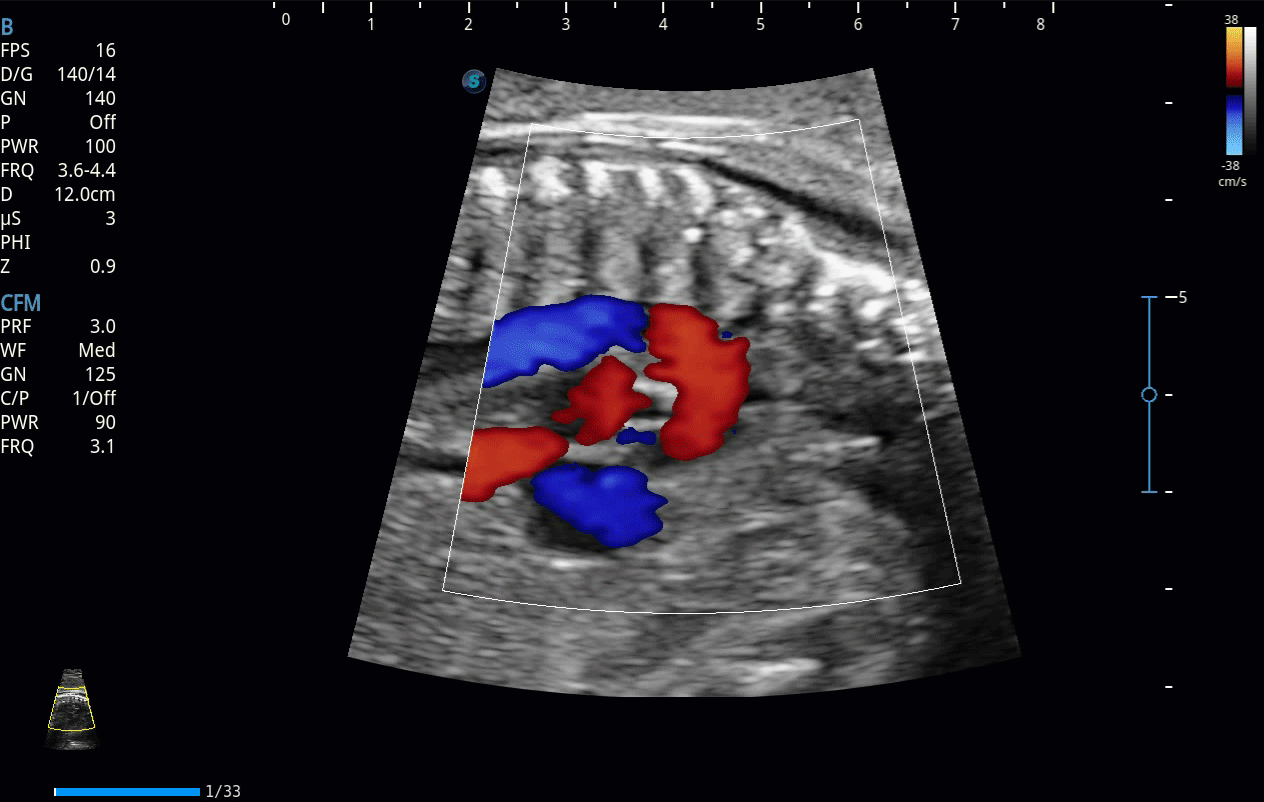

SR Flow高分辨率血流成像

高分辨率血流成像技术提高了对低速血流信号的检测能力。在提高空间分辨率的同时,也克服了血流外溢现象,为用户提供更加真实的血流动力学信息。

临床图像